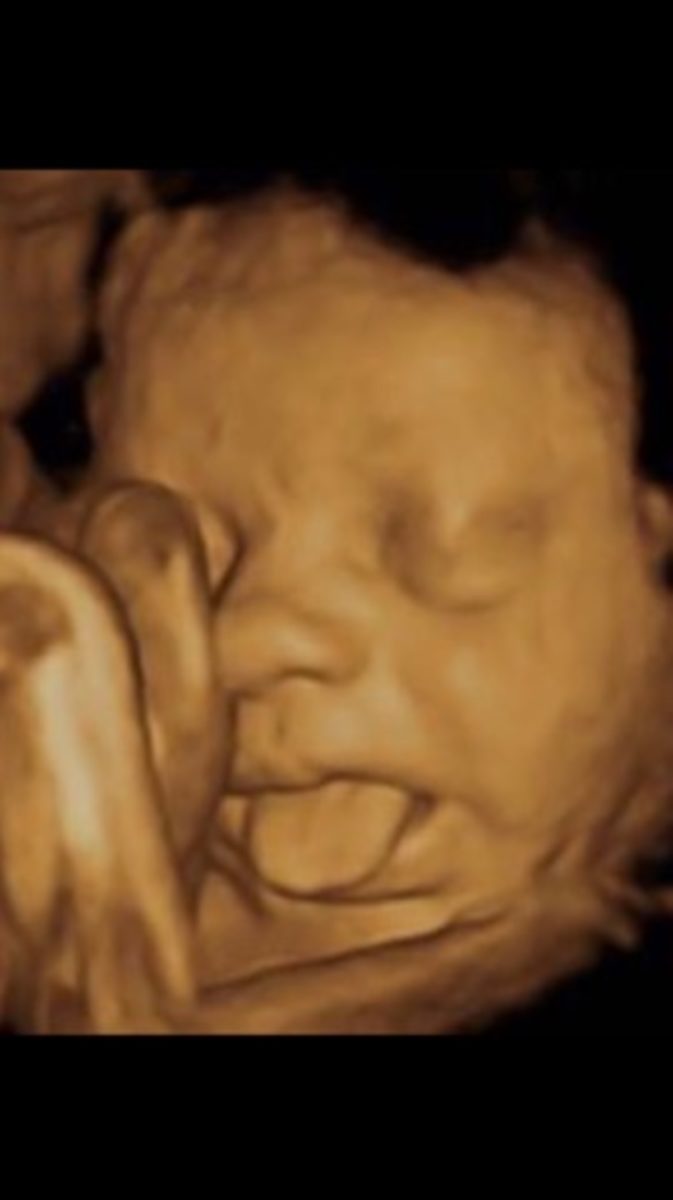

«Κανένα μυστικό δεν έχουν πλέον οι εκφράσεις του εμβρύου στη μήτρα, μιας και υπάρχει ο τετραδιάστατος υπέρηχος, που αποτυπώνει πιστά κινήσεις, εκφράσεις, χαρακτηριστικά του προσώπου αλλά κυρίως την ανατομία προσώπου, σώματος και άνω και κάτω άκρων». Αυτό υπογραμμίζει ο Μαιευτήρας, Χειρουργός-Γυναικολόγος Δρ. Νικόλαος Σκαρτάδος, αναφορικά με τις δυνατότητες που έχει η τετραδιάστατη απεικόνιση, όχι φυσικά μόνο για τα …φωτογραφικά ενσταντανέ και την καταγραφή του φύλου, αλλά κύρια για τα σοβαρά απεικονιστικά οφέλη που έχει για τη συνολική υγεία του κυοφορούμενου εμβρύου.

Όσο ελκυστική όμως και αν είναι η «φωτογραφική» απεικόνιση του εμβρύου και η τρυφερότητα που κινητοποιεί στους υποψήφιους γονείς, για τους γυναικολόγους είναι ιδιαίτερα σημαντική η λειτουργία της καρδιάς και των αγγείων που «αποκαλύπτονται» στις δυνατότητες του 4d υπερήχου, δίνοντας «όπλα» έγκαιρης διάγνωσης για οποιοδήποτε πρόβλημα προκύψει, έτσι ώστε πλέον να έρχονται στο φως με πληρότητα οι όποιες ανατομικές βλάβες εμφανίζει η ενδομήτρια ζωή του εμβρύου.